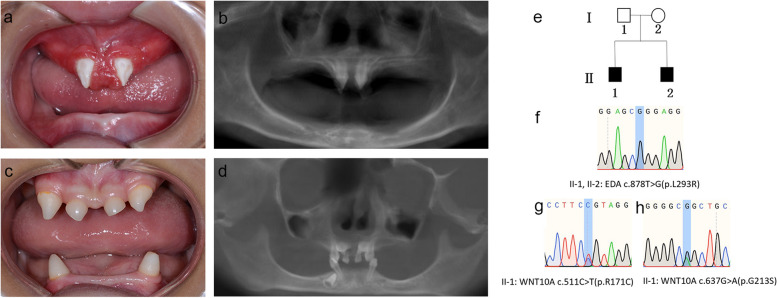

兩名分別為11歲和8歲的親兄弟因先天性牙齒缺失被轉(zhuǎn)診至同佳學(xué)基因具有合作關(guān)系的武漢大學(xué)口腔中心就診。經(jīng)患兒母親及兩名患兒本人簽署知情同意書(shū)后,醫(yī)護(hù)人員收集了兩位患兒的病史資料,拍攝了相關(guān)臨床照片,并采集了外周靜脈血樣本外送到佳學(xué)基因檢測(cè)進(jìn)行致病基因鑒定基因解碼分析。這對(duì)兄弟被診斷為低汗性外胚層發(fā)育不良(HED),均表現(xiàn)出典型的臨床特征,包括少牙(hypodontia)、毛發(fā)稀疏(hypotrichosis)、少汗(hypohidrosis)以及面部發(fā)育異常(facial dysmorphism)。有趣的是,哥哥的牙齒發(fā)育不全明顯比弟弟更為嚴(yán)重。哥哥下頜完全無(wú)牙,僅保留上頜兩顆中切牙;而弟弟則仍有部分前牙萌出。

體格檢查顯示,這對(duì)兄弟均表現(xiàn)出頭發(fā)稀疏、牙齒缺失及汗腺發(fā)育不良(圖1a-d)。兩人均具有X連鎖低汗性外胚層發(fā)育不良(HED)的典型面容特征:鞍鼻、嘴唇厚大、下頜尖翹以及眼周黑眼圈。

口腔檢查及錐形束CT(CBCT)掃描結(jié)果提示,哥哥(II-1)的所有乳牙及大多數(shù)恒牙均先天缺失,僅保留兩顆錐形上中切牙(#11、21)(圖1a-b)。由于下頜牙列完全缺失,他無(wú)法正常咀嚼或建立咬合關(guān)系。

弟弟(II-2)尚保留6顆乳牙(#51、53、61、63、73、83)及3顆恒牙胚(#11、21、43)(圖1c-d)。

Fig. 1

圖1:HED兄弟患者的牙齒特征與面部表現(xiàn)

a-b:**兄長(zhǎng)(II-1)**的口腔狀況及全景X線片。

c-d:弟弟(II-2)的口腔狀況及全景X線片。

e:家系圖,黑色方塊代表HED患者。

f:DNA測(cè)序圖譜顯示兩位兄弟(II-1,II-2)攜帶

EDA基因雜合變異c.878T>G(p.L293R)

。

g-h:兄長(zhǎng)(II-1)同時(shí)攜帶兩個(gè)WNT10A基因雜合變異:c.511C>T(p.R171C)和 c.637G>A(p.G213S)。

在兩兄弟中均檢測(cè)到EDA基因c.878T>G(p.L293R)的錯(cuò)義變異,但復(fù)合雜合型WNT10A基因變異(c.511C>T(p.R171C)和c.637G>A(p.G213S))僅在兄長(zhǎng)中發(fā)現(xiàn)。

母親臨床表型正常,未出現(xiàn)毛發(fā)、汗腺或牙齒相關(guān)異常。WES檢測(cè)顯示其為EDA基因c.878T>G雜合變異及WNT10A基因c.511C>T雜合變異的攜帶者。上述結(jié)果均經(jīng)Sanger測(cè)序驗(yàn)證(圖1e-h)。